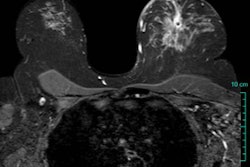

| False-negative case for all reviewers: 76-year-old woman with invasive ductal carcinoma. Above, craniocaudal mammogram obtained four years before study in which mass (arrow) was excised and was found to be benign (fibrocystic changes without atypia) at histology. Middle, screening mammogram, craniocaudal view, two years before study shows postsurgical changes. Below, screening mammogram, craniocaudal view, at time of study in which increase in density at biopsy site was not detected by any of reviewers, although area was marked by CAD system. |